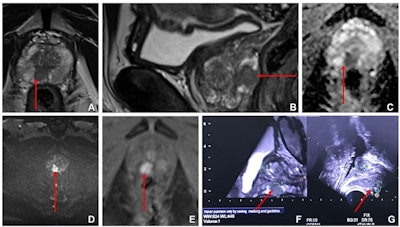

Images from multiparametric MRI of the prostate in a 60-year-old male participant show a focal lesion (arrow) in the right peripheral zone of the prostate at the mid-gland level. The lesion had low T2 signal on (A) axial and (B) sagittal T2-weighted MRI scans, marked corresponding restricted diffusion on (C) apparent diffusion coefficient and (D) high-b-value diffusion-weighted MRI scans, and (E) early contrast enhancement on a dynamic contrast-enhanced MRI scan. The lesion was a maximum of 13 mm on transverse axis with a bulge of the prostatic outline but no definite extraprostatic extension. This was scored as Prostate Imaging Reporting and Data System 4. Fused (F) isovolumetric T2 sequence with (G) US image. Square marker A is placed at the level of proximal prostatic urethra as an anatomic landmark. Fusion core showed a Gleason score of 3+4 prostate cancer. Images and caption courtesy of the RSNA.